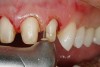

Figure 13  Preoperative view of a fixed partial denture that spanned anteriorly from tooth No. 18 to tooth No. 21. There was a minor biologic width encroachment on the distal aspect of the anterior abutment, tooth No. 21. The anterior abutment also had recurrent facial decay apical to the restorative margin and a lack of attached gingiva on the facial aspect.

Figure 13